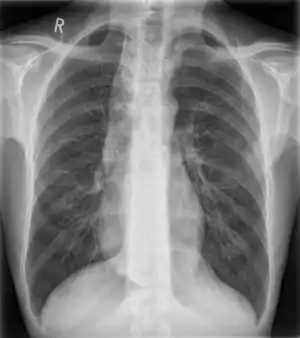

![]() | |

| Widened mediastinum in a patient with achalasia | |

Widened mediastinum/mediastinal widening is where the mediastinum has a width greater than 6 cm on an upright PA chest X-ray or 8 cm on supine AP chest film.[11]

A widened mediastinum can be indicative of several pathologies:[12][13]